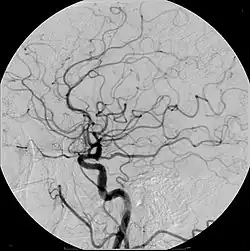

| Cerebral Angiogram obtained using an iodine based contrast medium | |

Cerebral atherosclerosis is a type of atherosclerosis where build-up of plaque in the blood vessels of the brain occurs. Some of the main components of the plaques are connective tissue, extracellular matrix, including collagen, proteoglycans, fibronectin, and elastic fibers; crystalline cholesterol, cholesteryl esters, and phospholipids; cells such as monocyte derived macrophages, T-lymphocytes, and smooth muscle cells.[1] The plaque that builds up can lead to further complications such as stroke, as the plaque disrupts blood flow within the intracranial arterioles. This causes the downstream sections of the brain that would normally be supplied by the blocked artery to suffer from ischemia.[2] Diagnosis of the disease is normally done through imaging technology such as angiograms or magnetic resonance imaging. The risk of cerebral atherosclerosis and its associated diseases appears to increase with increasing age;[3] however there are numerous factors that can be controlled in attempt to lessen risk.[4]

Due to positive remodeling the plaque build-up shown on angiogram may appear further downstream on the x-ray where the luminal diameter would look normal even though there is severe narrowing at the real site. Because angiograms require x-rays to be visualized the number of times an individual can have it done over a year is limited by the guidelines for the amount of radiation they can be exposed to in a one-year period.[2]